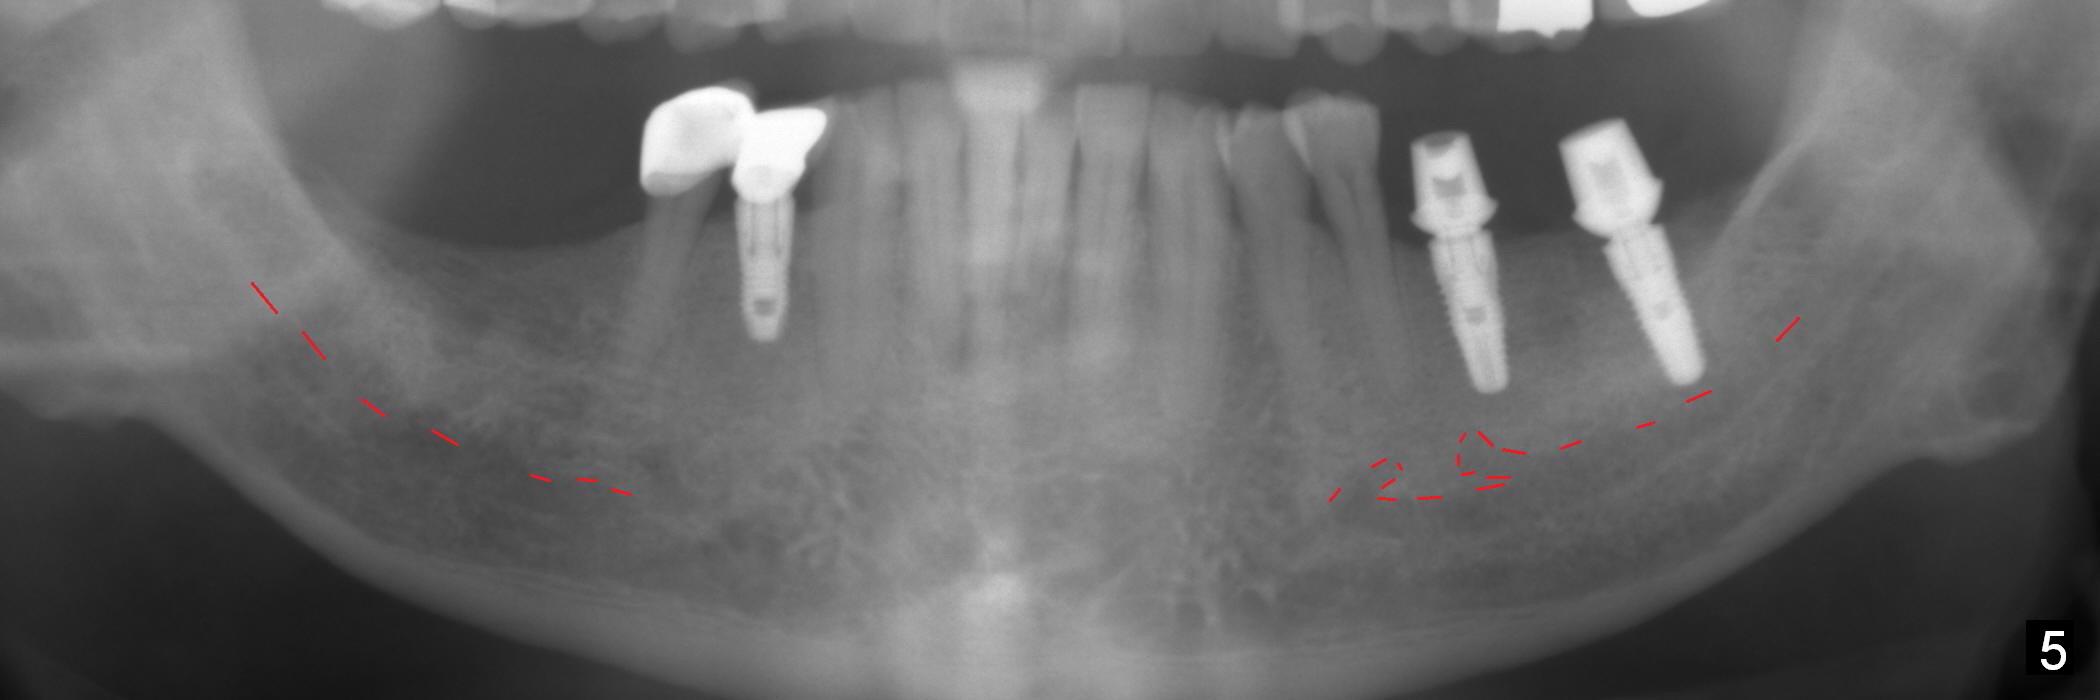

In fact, initial depth for #18 and 19 is 12 mm, quite close to the Inferior Alveolar Canal at #18 (Fig.3 (red dashed line: the superior border of the former). By mistake, the implant at #18 is placed a little deeper than necessary, since the buccal bone is inferior to the lingual one (Fig.4; 5.3x12 mm vs. 5.0x12 mm for #19). As planned, panoramic X-ray is taken immediately postop. Bone height at the 2nd molar decreases drastically as compared to that of the 1st molar, especially on the right side (Fig.5 (abutments: 6.8x5(2) mm for #19, 7.8x5(3) for #18, respectively)). For #30,31 implant placement, initial depth will be 10 and 8 mm, respectively. Follow it faithfully. The implant at #31 could be as large as 5.9 or 6.4 mm to compensate for the length.

One month later, the patient returns for #30 and 31 implant placement. As planned, the initial depth is 10 and 8 mm (Fig.6). What is unexpected is deficiency in ridge width. Narrower implants (as compared to those on the left) are placed (Fig.7: 4.5x12 and 4.5x10 mm). With shorter implants, the implants are later placed deeper (as shown by arrows in Fig.7) so that almost all of the microthreads are buried in the bone. It is expected that there is less chance of thread exposure postop. The later turns out to be true 3.5 months postop (Fig.8 with 6.8x5(3) mm abutments). It appears that the abutment margin is supragingival (white dashed line: gingival margin) and should be trimmed prior to impression. Or change the abutments to ones with shorter cuff. It may be so for those at #18 and 19 (Fig.9: 4 months postop). Custom full arch trays will be used for impression with bite registration. In fact the mesial margin of #19 abutment is ~ 2 mm subgingival. A longer-cuff abutment is used (6.8x5(3) mm) at #19 before impression.